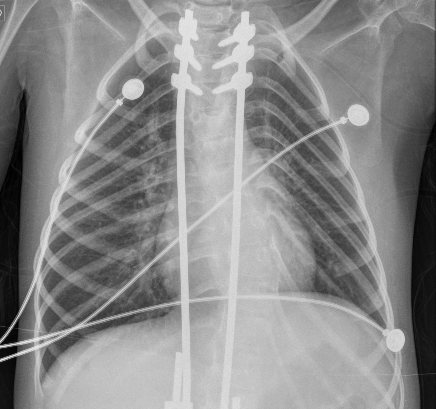

El primer día de internación, se solicitó una radiografía, que evidenció una atelectasia masiva del pulmón izquierdo (Figura 1). En este contexto, se optimizó la THB e interfaz de VNI. Para optimizar la presurización del sistema respiratorio, se cambió la interfaz nasal por una oronasal. El paciente permaneció con su equipo de VNI durante las 24 horas y solo se desconectó para realizar THB. Se monitorearon los signos vitales con el objetivo de mantener una saturación ≥94 % con la menor FiO2 posible. Como parte del plan de THB, se programó ventilación percusiva intrapulmonar (VPI) y CA dos veces al día durante cinco días consecutivos. Se utilizó un equipo de VPI The Impulsator® de Percussionaire con circuitos Phasitron®. Se emplearon 10 minutos en modo easy para favorecer la movilización de secreciones más distales y 10 minutos en modo hard para garantizar el reclutamiento alveolar. Se utilizó una relación I/E de 1:1 o 3:1, según tolerancia, con un rango de presión de la vía aérea entre 10-30 cmH2O y una presión de trabajo de 2-4 bares. Se continuó con CA, con una presión de insuflación de +30 cmH2O y una presión de exuflación de -40 cmH2O, junto con asistencia manual de la tos, con el objetivo de movilizar secreciones de vías aéreas proximales. En el segundo día, ante la ausencia de mejoría, se optimizó el equipo de soporte ventilatorio cambiando la VNI domiciliaria por un equipo de soporte vital. Se colocó un Trilogy 202 (Respironics®) en modalidad binivel, con monorama a fuga, en modo asistido controlado por presión, con humidificación activa y una interfaz facial total. En el tercer día, no se implementaron cambios en la programación de la VNI, y se continuó con la misma THB. En el cuarto día, se interconsultó al servicio de endoscopía respiratoria, quienes otorgaron un turno a la brevedad para realizar una fibrobroncoscopía con intubación e instilación de alfa dornasa, junto con VPI en línea con ventilación mecánica, como método invasivo de resolución de atelectasias. En el quinto día, se realizó una nueva radiografía, que mostró una reducción significativa del área atelectásica (Figura 2), lo cual se objetivó con mejoría clínica. Esto permitió descender las presiones, y se volvió a su programación habitual. Asimismo, se finalizó el uso de la VPI y se continuó únicamente con CA y asistencia manual de la tos. Después de 24 horas, el paciente estaba llevando a cabo dos períodos de 3 horas de desconexión de la VNI a aire ambiente. A las 48 horas, se logró la desvinculación de la VNI diurna, con reconexión nocturna a su equipo domiciliario e interfaz nasal. En el séptimo día, se confirmó la resolución de la atelectasia en la radiografía (Figura 3), quedando suspendida la intervención de endoscopía respiratoria. En el octavo día, se le otorgó egreso hospitalario. En la Figura 4, se resume la evolución del paciente.